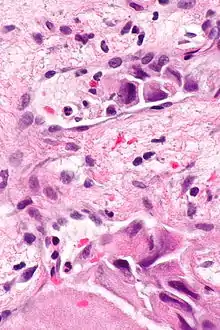

Micrograph showing lymphovascular invasion (top of image) in a case of laryngeal cancer. H&E stain.

Lymphovascular invasion (LVI or lymphovascular space invasion) is the invasion of a cancer to the blood vessels and/or lymphatics.